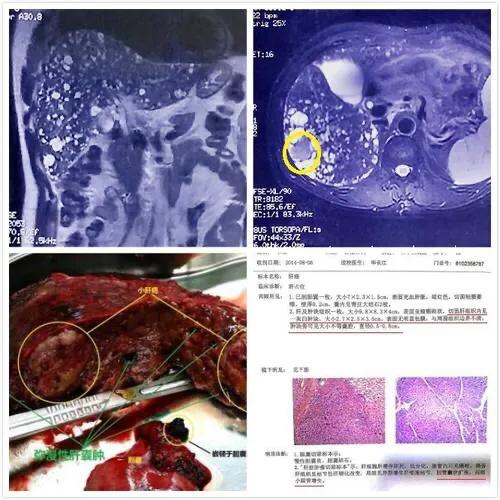

En cas de kystes hépatiques inexpliqués, il est conseillé de se rendre à l'hôpital pour une tomodensitométrie améliorée du foie et de consulter un chirurgien hépatobiliaire pour mieux comprendre la situation. Il ne faut pas être comme le patient que j'ai rencontré dans l'article précédent, qui était déprimé tous les jours jusqu'à ce qu'il connaisse la vérité.

L'examen de la fonction hépatique est généralement normal, l'examen échographique de la zone hépatique peut révéler plus d'un liquide de sécurité. La tomodensitométrie ou la scintigraphie nucléaire peuvent également vérifier la présence de kystes hépatiques multiples, en plus de déterminer que les kystes hépatiques multiples n'ont pas de lésions substantielles.